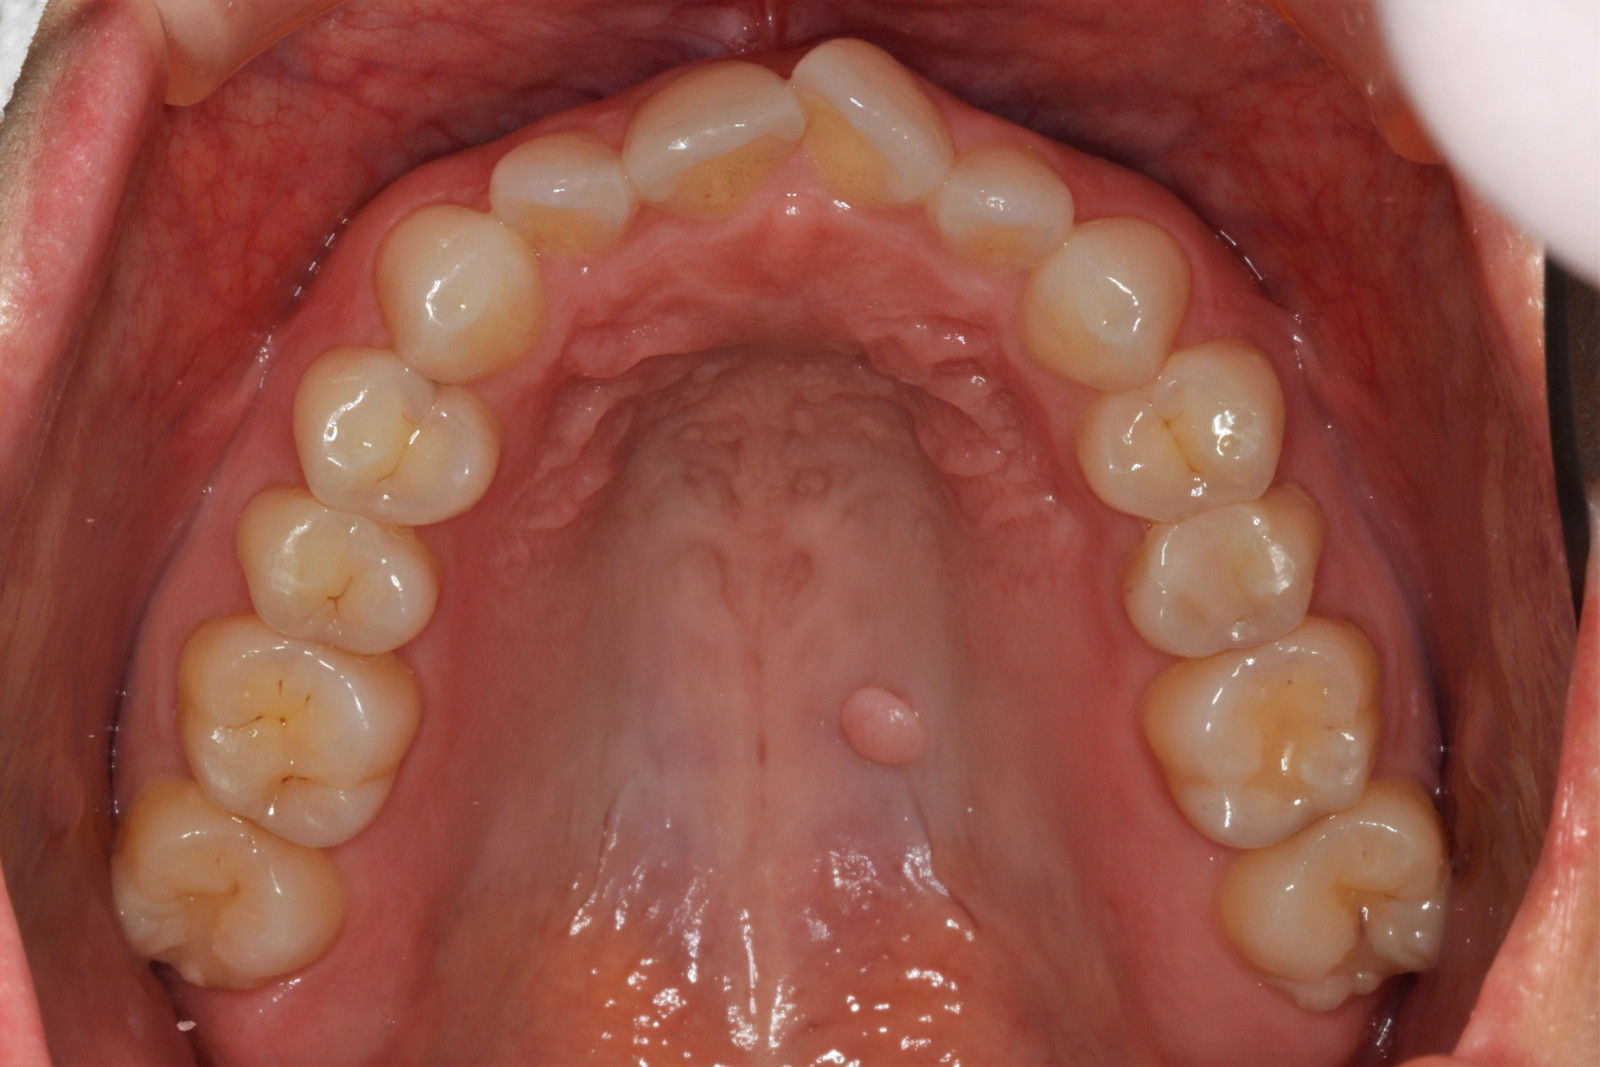

問診を行い、お口の悩みや希望を確認します。レントゲン撮影や口腔内写真の撮影など、必要に応じた精密検査を行います。